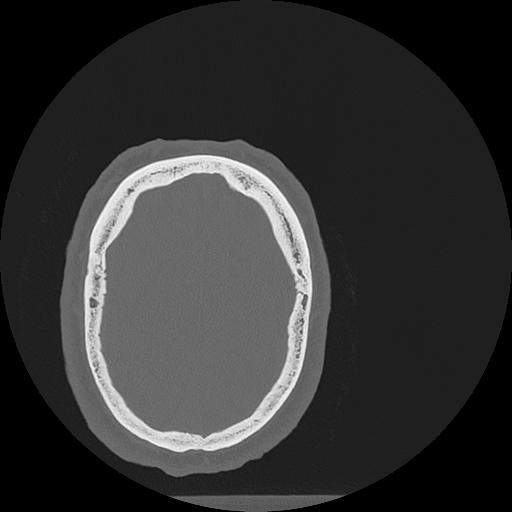

7 HUESO,,Vol,0.5,HUESO,,